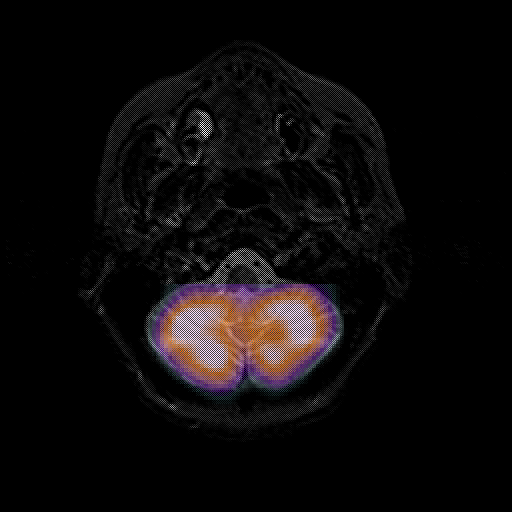

overlay 1: Slice 8

Slice 8

MRCBFCBF with